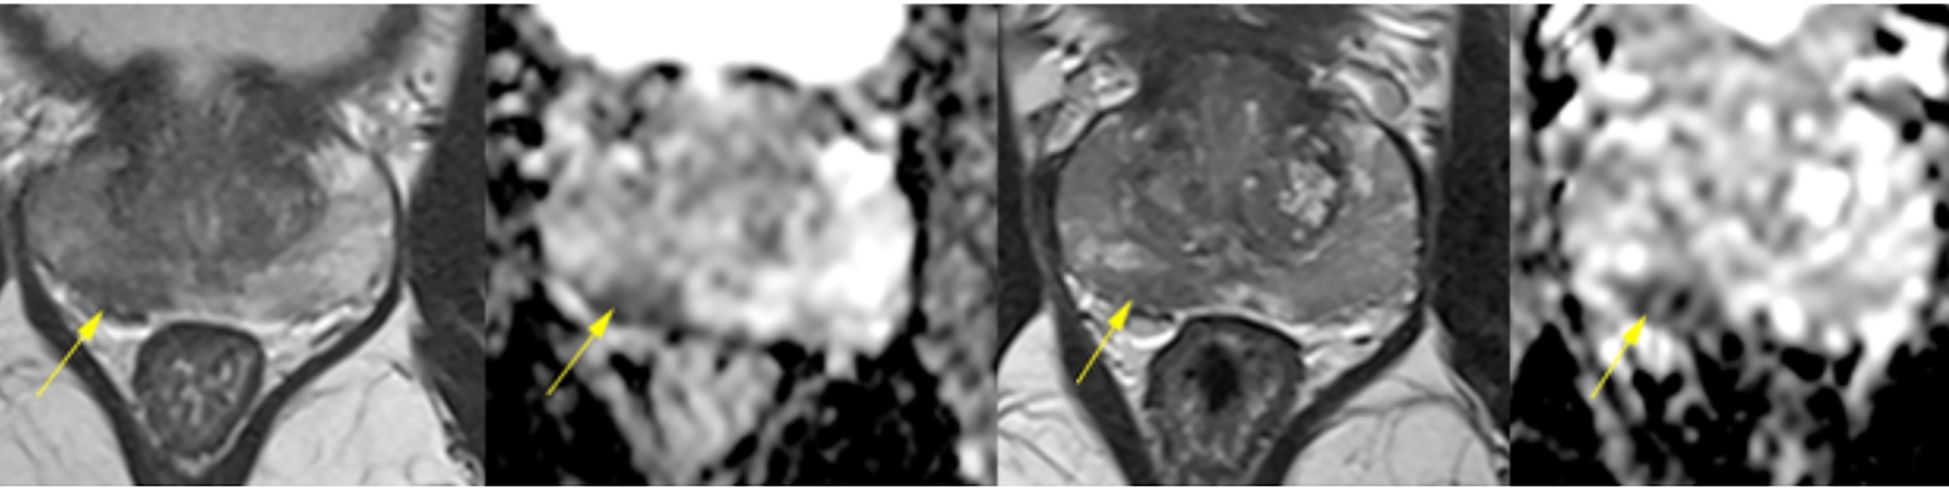

In June 2022, during a second confirmed SARS-CoV-2 infection, he developed prostatitis with perineal pain, weak urinary stream, nocturia, and PSA elevation (peak 7.9 ng/mL in July 2022). Multiparametric MRI performed on June 22, 2022, and repeated on December 26, 2022, revealed diffuse PI-RADS 4 changes in the peripheral zone, predominantly on the right, interpreted as inflammatory or infectious in origin (Figure 1). Symptoms improved after antibiotic therapy, while persistent LUTS due to prostatic enlargement were managed with finasteride and doxazosin, which were continued until biopsy.

Four-panel axial multiparametric prostate MRI comparing June 22, 2022 and December 26, 2022. In each pair, the left image is T2-weighted and the right is diffusion/ADC. Yellow arrows indicate areas of diffusely low T2 signal within the peripheral zone, more pronounced on the right, forming elongated, ill-defined, confluent regions without a discrete nodule. On diffusion/ADC, a small focus of restricted diffusion at the right base (~1.2 cm) is highlighted. Across timepoints, the pattern appears bilateral and stable, consistent with inflammatory/prostatitis-like changes, rather than a focal mass.

Figure 1. Multiparametric prostate MRI scans from June 22 and December 26, 2022, demonstrating diffuse and heterogeneous low signal intensity in the peripheral zone, predominantly on the right, with confluent, ill-defined elongated areas lacking discrete nodules. Both scans revealed diffuse early contrast enhancement and restricted diffusion at the right base (1.2 cm), consistent with PI-RADS 4 classification. The stability of these nonspecific findings over time, along with their bilateral distribution, suggested an underlying inflammatory or infectious process rather than malignancy.